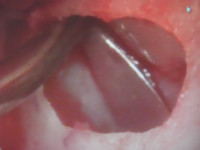

今日のオペは入れ歯固定用のインプラントの埋入オペでした。

ただこの部位は上顎洞底から歯槽頂までの厚みがありませんでしたので、サイナスリフトして骨造成を行い、同時法にてインプラント埋入致しました。